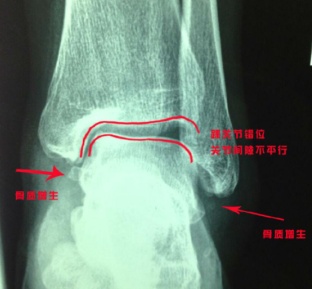

那是因为损伤的韧带没有完全修复,踝关节一直处于不稳定的状态,踝关节为了增加稳定性产生了肌肉代偿。久而久之,足踝肌肉常常会产生疲劳感,这会使踝关节更加不稳,出现“习惯性扭脚”。长此以往,关节会出现错位和骨质增生。